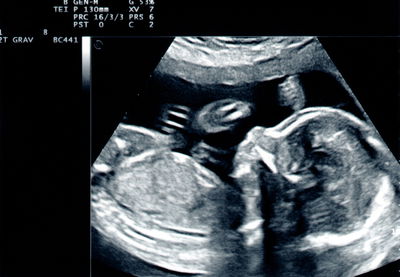

הבית ברוך השם מלא בקולות של שמחה, העריסה תופסת מקום מרכזי בבית, והידיים שלך? הן כנראה עסוקות מסביב לשעון. אחרי לידה, אנחנו נוטות לשים את עצמנו בסוף הרשימה. אבל האמת היא שכדי שתוכלי להמשיך לדאוג לכולם בנחת, הגוף שלך זקוק ל"תחזוקת מונע" (הריון ולידה)

ל אף שמדובר בתסמין נפוץ מאוד, עדיין אפשר לנסות להקל על הכאב וליהנות מהיריון נעים יותר וכואב פחות. כמו בלא מעט דברים המשפיעים על הבריאות שלנו, גם כאן התשובה טמונה בפעילות גופנית. באמצעות חיזוק שרירי הליבה וקיום אורח חיים פעיל ככל האפשר, כמו גם העלאה בריאה במשקל, עשויים לסייע ליציבה ו"לנהל" את העומס נכון ובכך להשפיע על כאבי הגב (הריון)